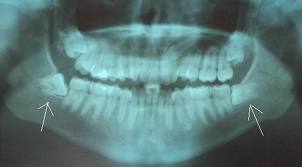

saKit

Aku rase cam mimpi..

Mulut aku x bleh bukak..tekak aku rase perit..

Aku cam Nampak ade bintang2..aku konpius..

Kat mane ak nih?

Aku amek tempoh bertenang sambil julur2kan lidah..

Ape yg lidah aku rase ni..aku pegang lak dgn tangan..

Ooo..bibir aku..

hidup lagi aku..alhamdulillah..

ita amek plastic specimen sambil goyang2 depan aku..

nah gigi ko..4 batang..

fuhh..